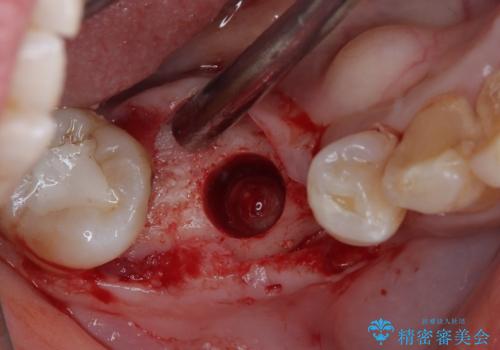

レントゲン写真より、歯根周辺に大きな病変(炎症により骨が溶けている状態)が認められたため、歯根が破折している可能性が示唆されました。

歯根が破折した歯は抜歯となるため、抜歯して病変の部分に骨が回復するのを待って、インプラントによる補綴治療を行うこととしました。

病変が大きかったことや、神経や血管が多く通る管が近いこともあり、抜歯即時埋入ではなく、骨の治癒が待ってから埋入を行う、従来の方法にてインプラント治療を行いました。